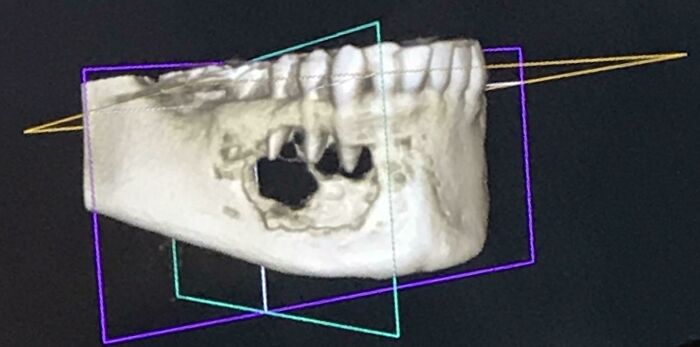

#1 Went In For Teeth Cleaning Last Month And Mentioned A Numb Feeling In A Tooth- I Was Shocked To Find A Tumor Eating My Jaw Bone

This photo is my CT scan. Biopsy surgery results were non-cancerous, thankfully. It’s been a real WTF month.